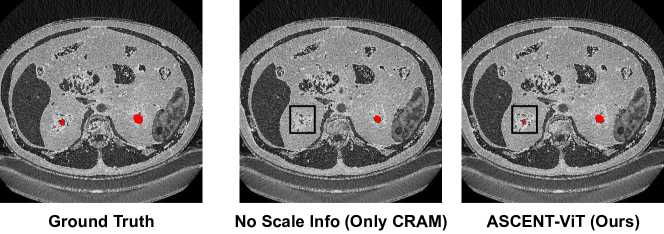

Refer to caption

Figure 5: Effect of Scale: Visualized concept annotations for a correctly classified sample from KITS. As seen, ASCENT-ViT identifies small ‘cyst’ annotation much more accurately (Acc=91.2%) than only CRAM (Acc=88.4%) where no scale information is utilized.

True Positive Rate (TPR): For CUB200 and AWA2, we observe that pixel-wise TPR improves by similar-to\sim4% on CUB200 and similar-to\sim5% implying that ASCENT-ViT captures pixels of interest much better than only CRAM. In Fig 6, we demonstrate the effect on random test images where ASCENT-ViT captures concept annotations more effectively than only CRAM.

Pixel Accuracy: For KITS, we report total pixel accuracy which includes both concept and background annotations. Note that due to the sensitive nature of KITS, it is important to correctly identify both relevant (cysts) and irrelevant concepts (kidney surface). We observe ASCENT-ViT outperforms only CRAM by similar-to\sim1.5% over all architectures on KITS.